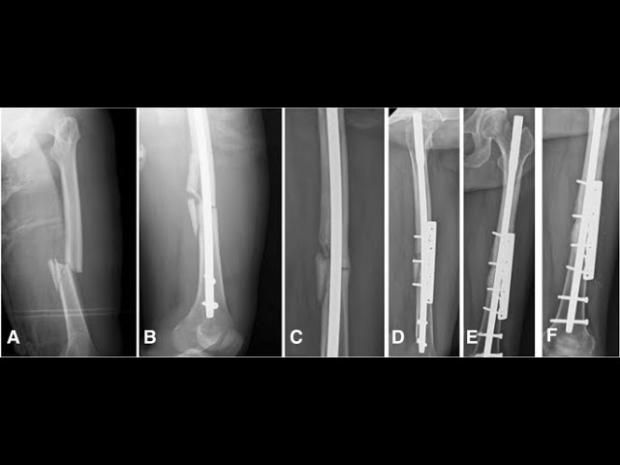

في واحدةٍ من أكثر الإصابات قسوة هذا الموسم، تعرض اللاعب الجزائري أحمد القندوسي، المعار من النادي الأهلي إلى سيراميكا كليوباترا، إلى كسرٍ مضاعف في الساق خلال مباراة أمام نادي فاركو، ليُصاب الذهول في المدرجات والصمت في المستطيل الأخضر، وكانت الإصابة عنيفة لدرجة أنها استدعت تدخلًا جراحيًا عاجلًا لتركيب مسمار نخاعي داخلي لتثبيت العظام، وهي من العمليات الدقيقة التي تُستخدم غالبًا في الحالات المعقّدة.

ونجحت العملية الجراحية التي خضع لها اللاعب، وتحتاج بعدها مرحلة دقيقة من التأهيل والعلاج الطبيعي، والتي تُعد حاسمة في تقرير مصير اللاعب وقدرته على العودة للملاعب بنفس القوة، وفي هذا السياق، كشف الدكتور أحمد علام، استشاري العلاج الطبيعي، في تصريحات خاصة لـ«الوطن»، تفاصيل المرحلة التي يعيشها اللاعب حاليًا، وخطوات التأهيل المنتظر اتباعها بدقة.

وأضاف علام أنّ التقييم المستمر باستخدام الأشعة هو الفيصل في تحديد مدى تقدم الالتئام، مشيرًا إلى أن أي استعجال في زيادة الأحمال قد يؤدي إلى مضاعفات خطيرة، أو تأخر التئام العظام، وهو ما يمثل كابوسًا لأي لاعب محترف.